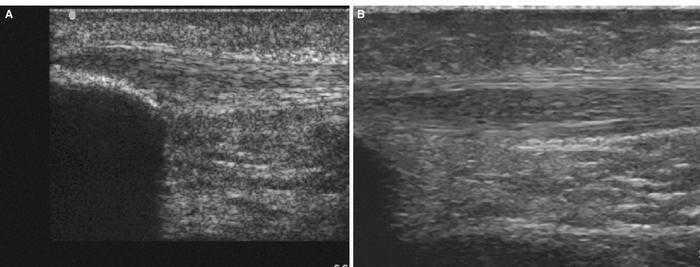

Utilizando el equipo E-A, en un corte longitudinal sobre el músculo gemelo externo a la altura del tercio superior (fig. 2A) se observa la referencia ósea que corresponde a la cortical del peroné, y en un plano superior no se aprecia discontinuidad focal de las fibras ni la presencia de un hematoma intramuscular, debido posiblemente al prolongado tiempo de evolución (1 mes). Por el contrario, con E-B se aprecia una zona hipoecoica en el vientre muscular del gemelo externo (fig. 2B), de aspecto irregular y lineal no visualizable con el E-A, lo cual facilita la confirmación ecográfica de la sospecha clínica.

Figura 2 A) Aspecto fibrilar normal en un corte longitudinal del músculo gastrocnemio externo sobre el peroné en una imagen de E-A. B) En un corte longitudinal con E-B se observa el área hipoecoica en el vientre del gemelo externo.